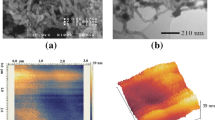

Morphological study of the electrode surfaces. Figures 1a, 1b shows the SEM images of the bare GCE and MWCNTs-GC modified electrode, respectively. As it is shown in Fig. 1b, many adsorbed MWCNTs are observed on the surface of the GCE.

The MWCNTs-GC modified electrode provides electroactive sites for the accumulation of fentanyl at open circuit potential. This electrode was used for the determination of fentanyl with a low detection limit using differential pulse adsorptive stripping voltammetric method. This electrode is simple to prepare, and the SEM images showed the presence of MWCNTs on the surface of the modified electrode. The overpotential for oxidation of fentanyl is decreased on the surface of this modified electrode compared to an unmodified electrode. Furthermore, the modified electrode indicates remarkable enhancement in the electrooxidation peak current of fentanyl in comparison to the bare GCE. This modified electrode was successfully utilized for the determination of fentanyl in real samples.